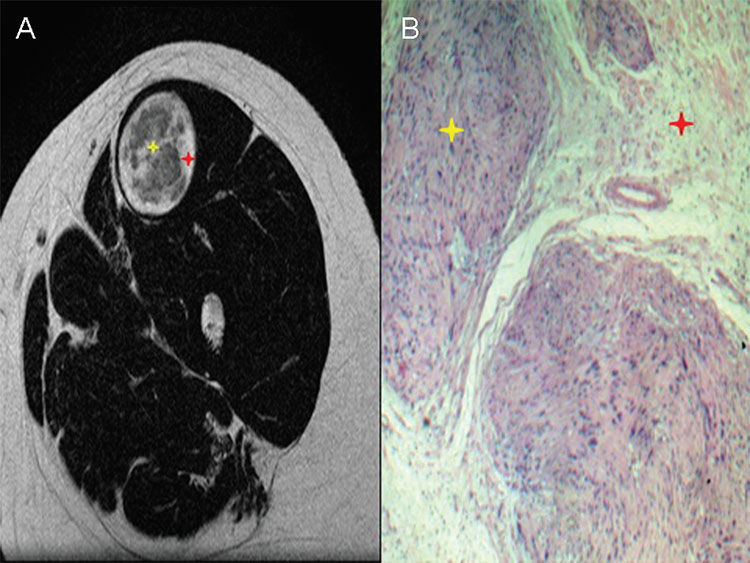

La distribución celular del target sign se observa con más frecuencia en los neurofibromas, mientras que en los schwannomas el componente celular tiene una distribución más aleatoria. Sin embargo, cuando el target sign es visualizado en los schwannomas, la zona central hipointensa corresponde a las células Antoni A y la zona hiperintensa periférica corresponde a las células Antoni B3 (Fig. 3). Las células Antoni A presentan un patrón más celular y las células Antoni B un patrón más hipocelular. En los casos de tumores malignos de nervios periféricos, las zonas que presentan el target sign contienen tejido benigno y el resto de las áreas del tumor representa la transformación maligna del tejido.3

(A) target sign de un schwannoma en resonancia magnética y (B) su correlato anatomopatológico. El área central hipointensa corresponde a la zona celular Antoni A (estrella amarilla), mientras que la zona periférica hiperintensa corresponde a la zona celular Antoni B (estrella roja).